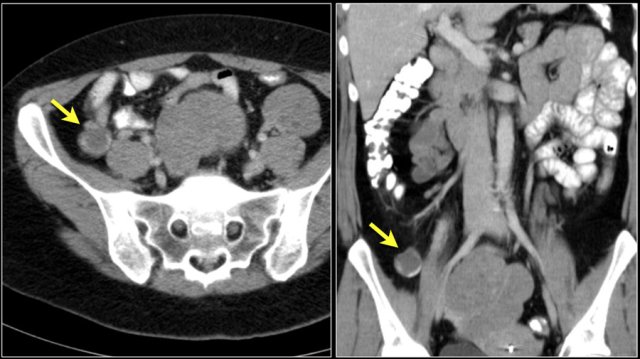

The images show a short obstructing circular mass in the jejunum (yellow arrow) with enlarged lymph node (red arrow).

This proved to be an adenocarcinoma.